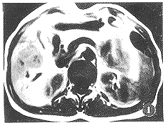

非轉移性癌性神經肌肉瘤半數的病例有腫瘤中心性潰瘍,加之血循環豐富,故破潰後常易發生上消化道出血。腫瘤可直接侵犯周圍組織,常累及大網膜及腹膜後,並經血行轉移,多見於肝,其次為肺。淋巴轉移不常見。

1.大體形態腫瘤大小不一,可單發或多發,直徑從數毫米至十餘厘米,甚或超過20cm,一般直徑在10cm左右,呈結節狀或分葉狀。較小的平滑肌肉瘤多位於壁內,外觀與平滑肌瘤相似,可向腔內隆起呈廣基無蒂,少數可呈蒂狀,其表面的黏膜往往有潰瘍形成,小的較表淺,直徑約0.2cm,大的可達5cm以上。較大的腫瘤常向腔外突出,少數呈啞鈴形,並可侵犯周圍臟器和組織。一般認為,腫瘤呈結節狀,向腔內或腔外生長,有囊性變或大而不規則的潰瘍者,多為平滑肌肉瘤。切面呈淡褐色或黃白色,經甲醛乙醇(福馬林)固定後呈淡褐紅色,可見到編織狀纖維束,並有壞死、出血及囊性變。